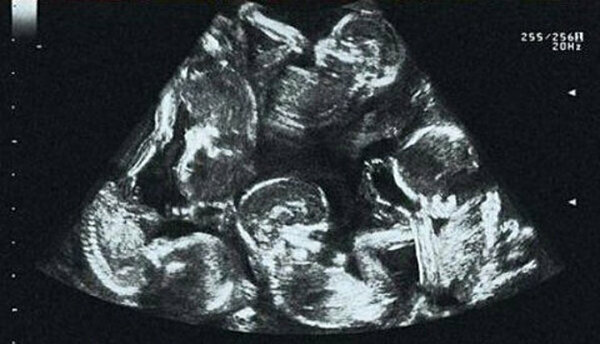

Když Alexandra Kinová zjistila, že je těhotná, měla z této dobré zprávy obrovskou radost. Těhotenství bylo dokonalé, protože žena byla mladá a zdravá. Aleksandra se ke svému stavu chovala velmi opatrně a něžně, a když při prvním ultrazvukovém vyšetření zjistila, že má v bříšku více než jedno dítě, reagovala na tuto zprávu klidně, protože dvojčata už měla z předchozího těhotenství. S manželem se těšili, že se stanou rodiči několika dětí najednou. Jak se však ukázalo, čekala na pár zcela neobvyklá zpráva. V průběhu těhotenství lékaři zjistili, že žena bude mít čtyři děti! Ale i tehdy Alexandra projevila klid, nedělala si starosti, ale rozhodla se pečlivěji a důkladněji připravit na nadcházející porod.

Žena podstoupila všechna plánovaná vyšetření. Během jednoho z těchto sezení se však zcela nečekaně objevil nový objev! Lékaři už napočítali pět dětí.

Aleksandra tomu nemohla uvěřit a rozplakala se. Vůbec ne ze strachu, ale ze štěstí. Koneckonců ne každá žena je pro takové poslání vesmírem vybrána - pět dvojčat se rodí jen jednou za několik století.

Narození těchto dětí sledovala celá země, protože podle statistik vedených od roku 1949 nebyl takový případ nikdy předtím zaznamenán. Alexandra porodila 4 syny a 1 dceru, kteří byli pojmenováni: Daniel, Michael, Martin, Alex a Teresa. Rodiče paterčat obdrželi mnoho gratulací a darů jak od obyvatel České republiky, tak od státu.